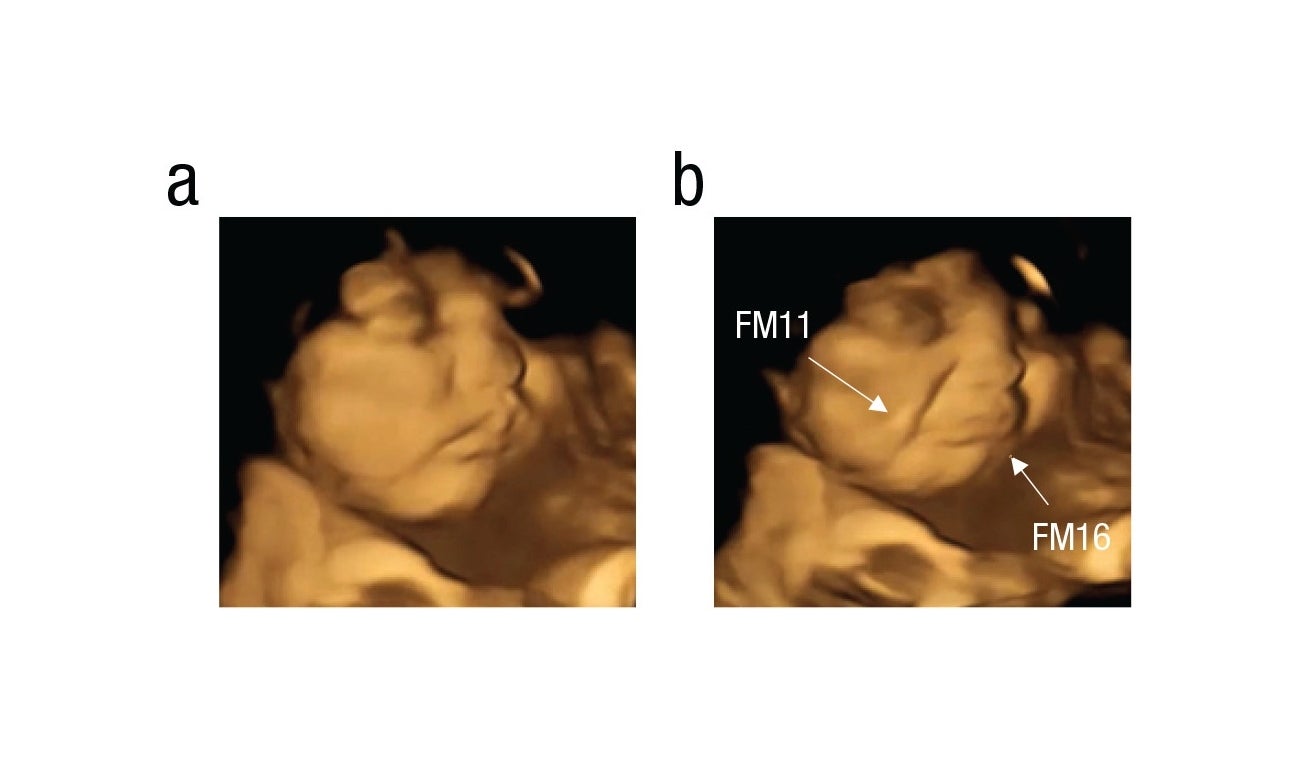

Aquellos que quedaron expuestos a la zanahoria hacían tirones de la comisura de los labios, lo que daba la impresión de que estuvieran sonriendo. Mientras que los expuestos a la col rizada hacían una mueca, como si estuvieran frunciendo el ceño.

Feto Zanahoria

Feto expuesto a la Zanahoria

Psychological Science